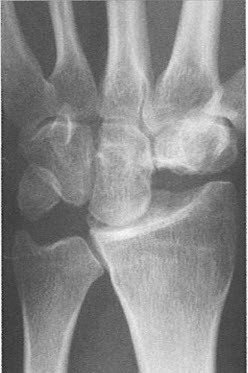

Eine Verdachtsdiagnose kann bereits durch die Patientenbefragung und das aktuelle Beschwerdebild gestellt werden. Gesichert wird die Diagnose einer Arthrose dann durch ein Röntgenbild. Findet sich nur eine leichte Arthrose, müssen möglicherweise Zusatzuntersuchungen durchgeführt werden. Bei fortgeschrittenen Arthrosen mit Gelenkzerstörung findet sich im Röntgenbild nur noch ein schmaler oder auch gänzlich fehlender Gelenkspalt (Abb. 1a bis 1c).